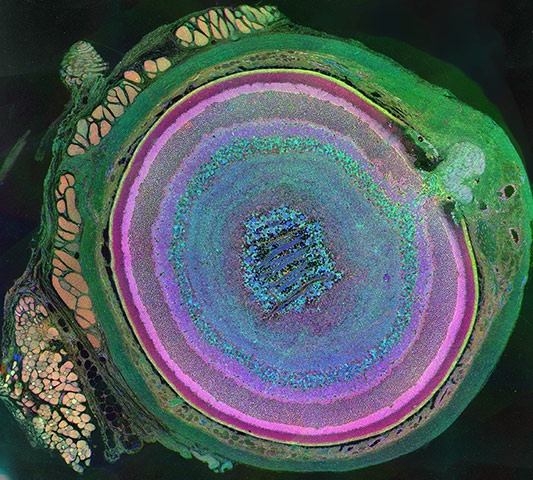

Metabolomic Eye (First Place, Photography). A section through a mouse retina, created using 'computational molecular phenotyping' Photograph: Courtesy of Bryan William Jones/The University of Utah/Moran Eye Center/Science